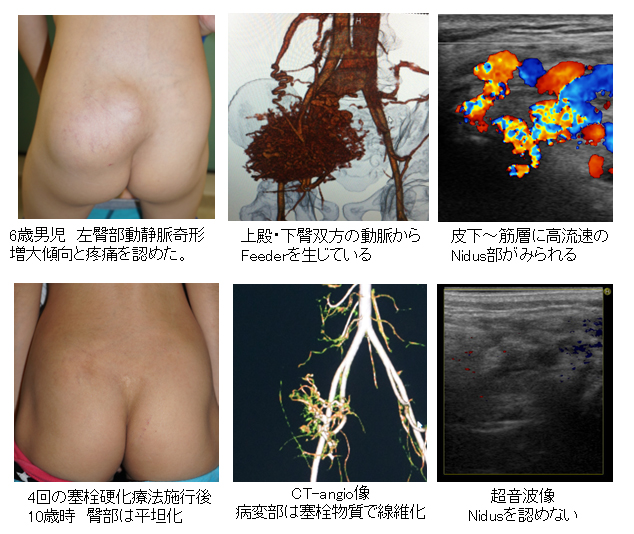

超音波検査(肝臓②) - たなべ内科クリニック(呉市広本町の。血管腫・血管奇形 ー診断と治療についてー | 横浜市立大学附属病院。03202608.jpg。他にも多数、出品しています♪よければ覗いてください☆#サクラBooks【商品について】・送料無料・即購入OK(コメント不要)・中古品ですが、通読に支障のない良好な状態です・書き込み無し・ご購入から1~2日以内に発送いたします・画像に掲載がない場合、付属品は無いものとお考えください・状態は画像にてご確認ください。血管腫 - Wikipedia。※写真と実物で色味に若干の差が出る場合がございます※本のコンディションは中身の状態を重視して判断しております。薬屋のひとりごと 1~13巻(11、12巻ドラマCD付限定特装版)。軽度のスレやキズなどの外装ダメージは記載・掲載を省略しています【ご確認事項】 •申し訳ありませんが、お値下げ交渉には対応しておりません。岩波文庫 三国志 全10巻 オリジナルパラフィン 赤帯付属 各種栞付きです。。•商品価格は、送料や手数料、メルカリ相場などを考慮し、あらかじめご検討いただきやすい金額で設定しております•お値段に関するコメントは削除させていただく場合がございます•価格は定期的に見直しておりますので、ご縁を感じていただけた際にぜひご検討くださいませ・商品状態はあくまで出品者の主観によるものです。【ポストカード付き】悪ノ娘 & 悪の大罪 全13巻セット。画像と説明をご確認の上、ご購入ください・発送は沖縄県から行います→ 地域によっては通常より到着にお時間を要することがあります→ 台風の影響で到着まで7~12日かかった事例もあります。宮部みゆき 『ブレイブ・ストーリー』愛蔵版 署名落款。気長にお待ちいただけますと幸いです・匿名配送(追跡・補償あり)でお送りします・ペット・喫煙者のいない環境で保管しておりますその他ご不明な点がございましたら、お気軽にコメントよりご質問ください「刻まれた21センチ 血管腫と共に生きる」玉元 三奈美#玉元三奈美 #玉元_三奈美 #本 #日本文学/評論・随筆